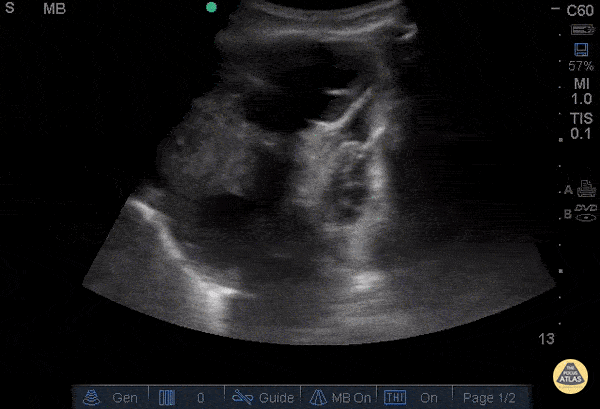

This is a clip of an elderly gentleman, who was called as a respiratory distress code while walking to clinic without his home oxygen. Initially, patient was tachycardic, tachypnic, and hypoxic to mid 80s on RA, however normotensive in mild respiratory distress, resolved with 3L O2 by nasal canula. This clip here was obtained by having the patient in the upright position, with the probe in the left lung base. You can see the diaphragm on the left side of the clip, with multiple loculated pleural effusions in left lung base adjacent to compressive atelectasis vs cardiac activity. The effusion was later drained, found to be a malignant effusion, with a subsequent biopsy showing a Non-Small Cell CA in the left upper lobe and Squamous Cell CA in the right upper lung. Chris Hanuscin, MD and John F. Kilpatrick, MD